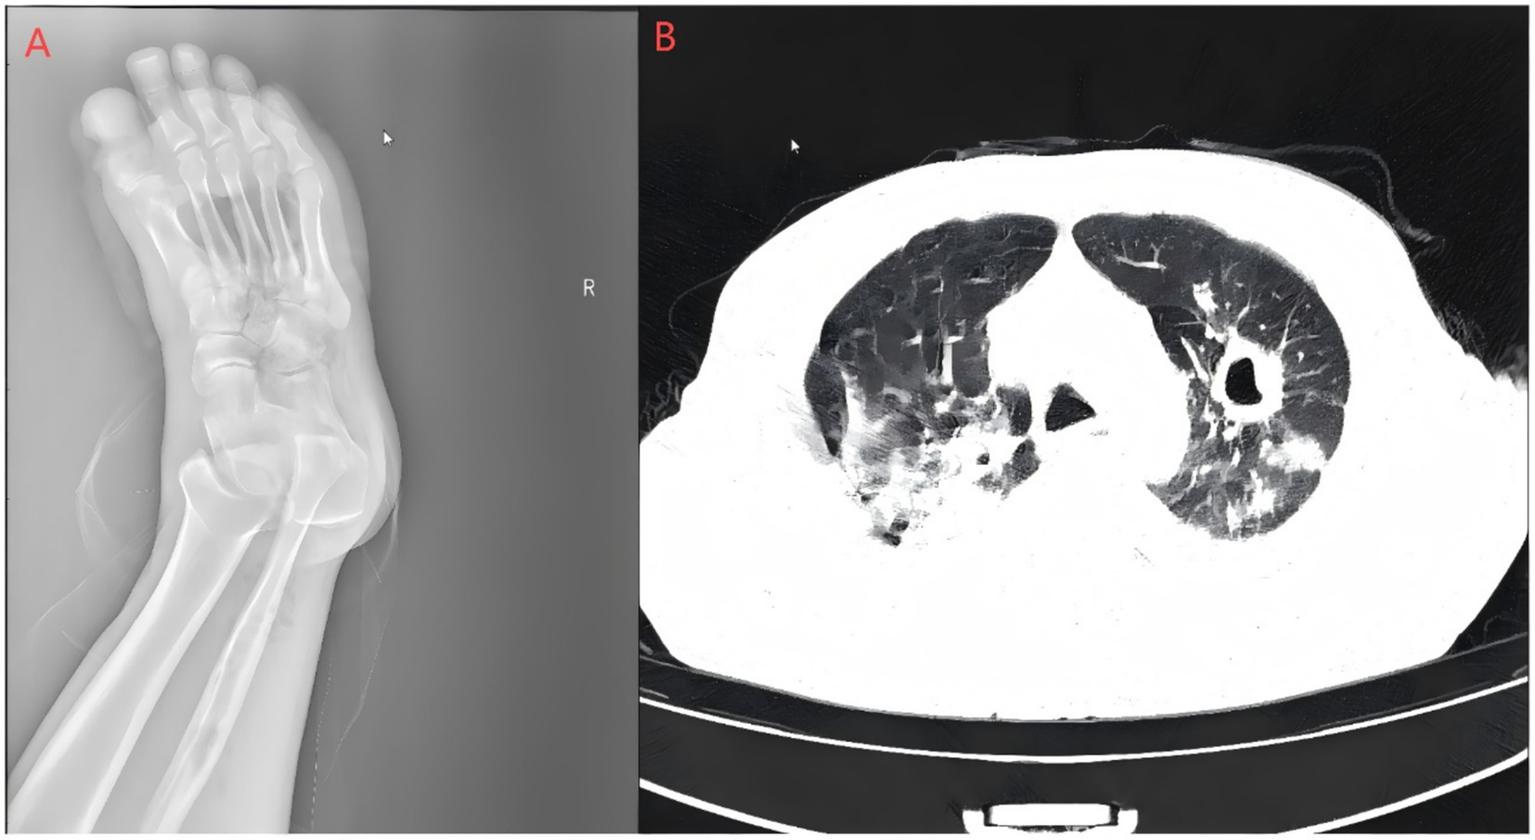

Laboratory and imaging findings: All initial investigations are summarized in Table Chest CT revealed lung infections with cavity formation bilaterally and a small amount of pleural effusion on both sides (Figure 2). MALDI-TOF confirmed A. turicensis and G. morbillorum (scores 2.26 / 2.42; Figure 3).

Figure 2

Right foot X-ray and pulmonary CT scan. (A) Bone resorption and destruction can be seen in the first toe of the right foot, and the soft tissue of the right foot is swollen and broken with gas accumulation; (B) polymorphic lung infections with cavity formation bilaterally and a small amount of pleural effusion on both sides. The Supplementary images are available upon reasonable request.